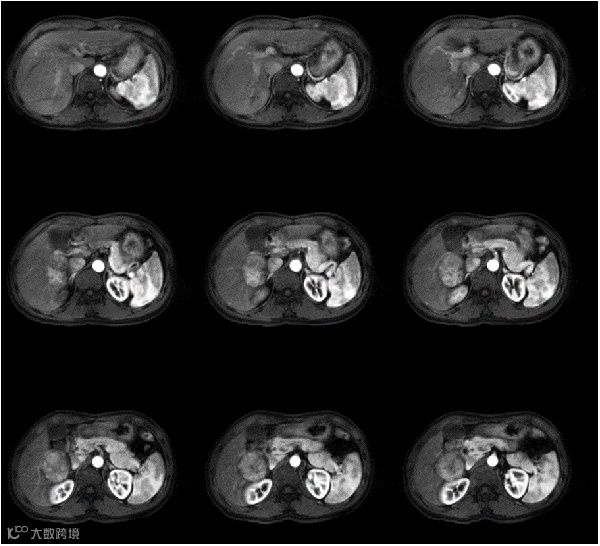

如果你问,1.5T磁共振如何兼顾临床与科研?奥泰医疗,作为中国超导磁共振产业创领者,他们今年展会的核心展品ASTA Venus 1.5T磁共振,便交出了答卷!

该设备搭载了全新的V-MAG硬件平台,独立数字化32通道实时无损传输数据,使得图像信噪比提高20%;且配备的41mT/m&204T/m/s高性能梯度系统,在确保图像空间分辨率和对比度达到最佳状态的同时,实现了更精准更稳定的成像;另有三“零”工艺磁体,生命周期内甚至无需添加液氦;加上高密度一体化柔性线圈,为靠谱而舒适的磁共振扫描打下坚实基础。

ASTA Venus 1.5T磁共振

有了V-MAG硬件平台作为高性能成像的核心保障,该磁共振设备还搭载了Bio-mapping精准定量平台,能够对肝脏、软骨和颅脑等关键部位进行精准定量分析;为了进一步提升工作效率,还配置了One Act智能工作流,实现了医学影像检查的自动化和智能化。

如果说用一句话说明这台1.5T磁共振,那就是“让基层医院用得起,三甲医院看得上”,ASTA Venus 1.5T的诞生,标志着磁共振技术领域迈入舒适化、精准化、智能化的全新时代。